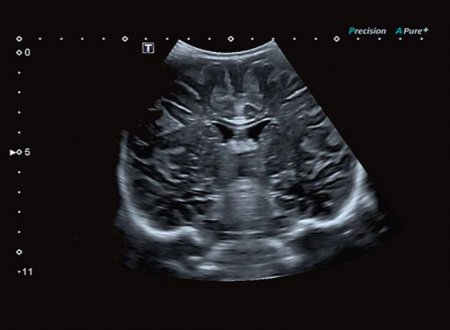

Режим дифференцированной тканевой гармоники (DTH) обеспечивает высокую детализацию глубоко расположенных структур. Поскольку в этом режиме за один импульс передаются сигналы на двух различных частотах, изображения обладают непревзойденным пространственным разрешением и контрастностью, а также большей глубиной проникновения.